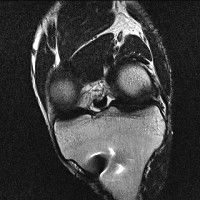

무릎 mri 간단히 봐주실 수 있으시나요 ㅠㅠ

안녕하세요 8년전 십자인대 수술하고 최근 무리한 운동에 무릎 불편감이 생겨서

mri 찍었습니다.

진단결과는 첫 찍은 병원에서 활액막염 이라는 진단을 받았습니다. 혹시 봐주실 수 있으실까요?

올라온 MRI가 단편적이라서 정확한 진단에 어려움이 있지만 십자인대에는 큰 이상이 있지는 않은것 같으며, 무릎관절내 물이 있는 것으로 보아 활액막염의 진단이 맞을 것 같습니다.

하지만 단편적인 영상이기 때문에 촬영병원에서 정확한 판독지 등을 받으시는 것이 좋겠습니다.